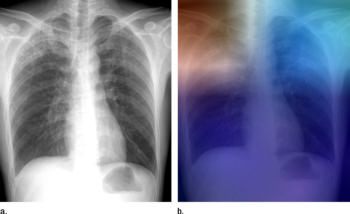

Figure 4 (a) Posteroanterior chest radiograph shows upper lobe opacities with pathologic analysis–proven active TB. (b) Same posteroanterior chest radiograph, with a heat map overlay of one of the strongest activations obtained from the fifth convolutional layer after it was passed through the GoogLeNet-TA classifier. The red and light blue regions in the upper lobes represent areas activated by the deep neural network. The dark purple background represents areas that are not activated. This shows that the network is focusing on parts of the image where the disease is present (both upper lobes).